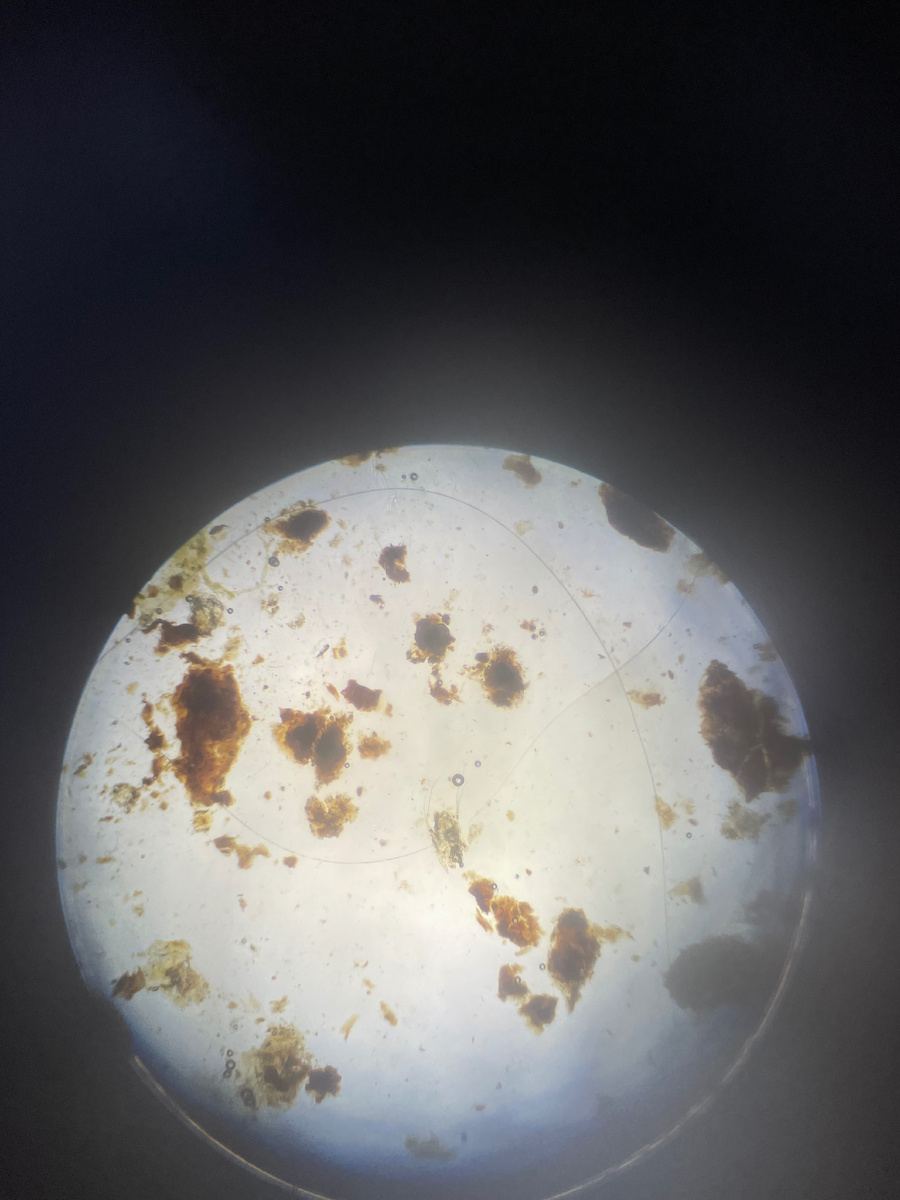

• Темно-коричневые выделения(похожи на кофейную гущу).

⚠ Важно! Похожие симптомы бывают при бактериальных и грибковых инфекциях, поэтому точный диагноз должен ставить ветеринар (под микроскопом).